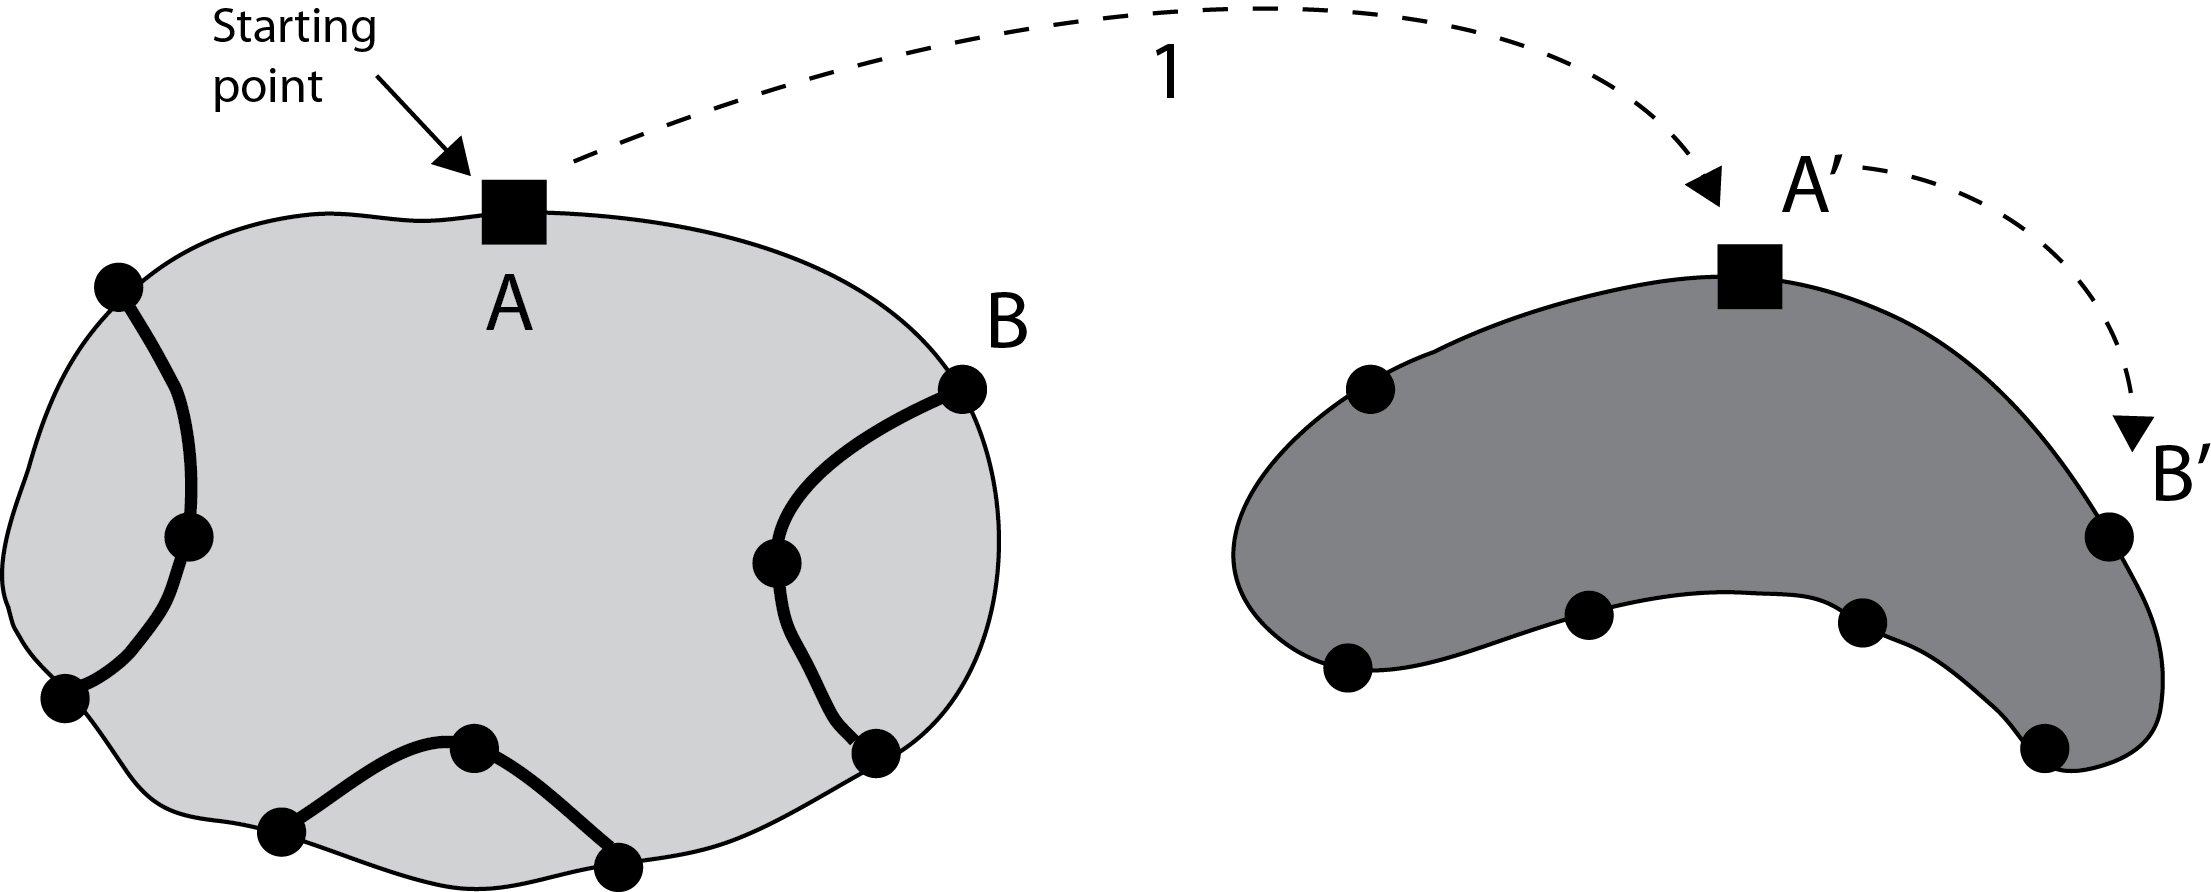

Mapping instead of Registration (Algorithm 3) – Finding the correspondent pixels in and consequently in , given the zonal coordinates in , seems to be a typical “registration” task. However, based on our experimental results we decided to not use registration algorithms for this purpose. The non-rigid registrations we tested were both time-consuming (which may not be a critical drawback) and inaccurate. Whereas one may use a specific registration algorithm in context of a familiar segmentation task, we do provide a quasi-non-rigid mapping procedure that is very fast, due to its simplicity, and can handle small irregularities quite easily. For this, first we do fix some points on the contour of the master gold (see Algorithm 4 in Appendix) and then map them to the ground-truth (see Algorithm 5 in Appendix) and segment (Algorithm 3; see Figure 3).